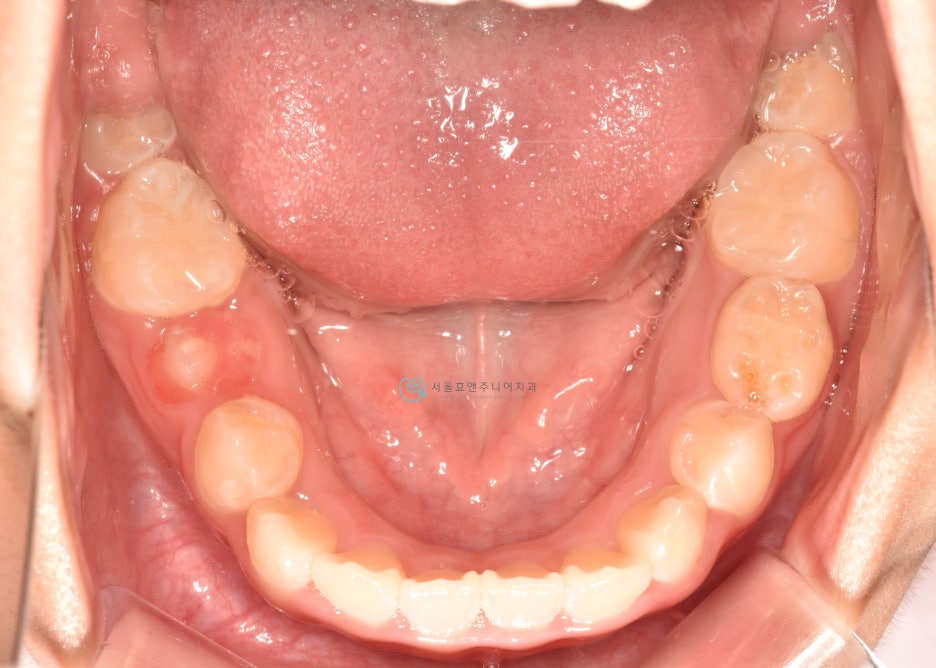

초진사진입니다

초진사진입니다. 11세 5개월 환아로, 반대교합을 보이고 있습니다. 반대교합으로 인해 치아가 부딪혀 치은퇴축(잇몸이 내려감)도 보이고 있네요.(화살표)